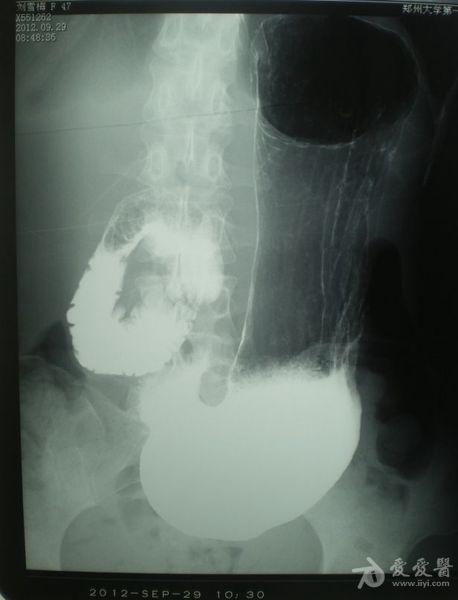

良性十二指肠瘀滞,等你分析 | 读片专栏855期

x线诊断要点丨十二指肠球部溃疡憩室十二指肠淤滞症

肠系膜上动脉压迫综合征(良性十二指肠瘀滞症)